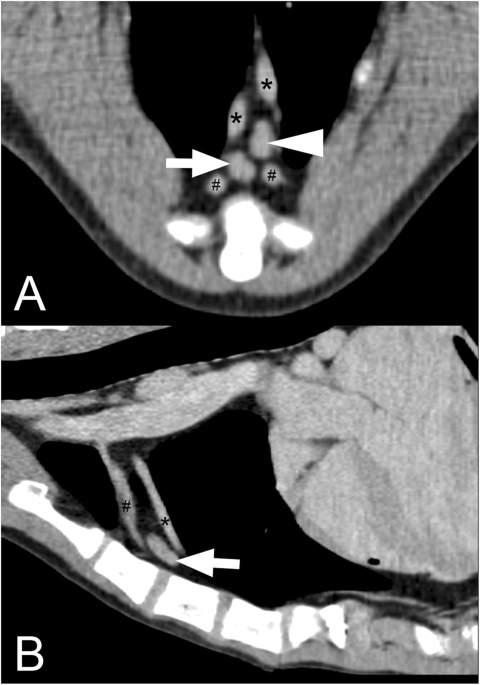

Computed Tomography Measurements Of Presumptively Normal Canine Sternal Lymph Nodes Bmc Veterinary Research Full Text